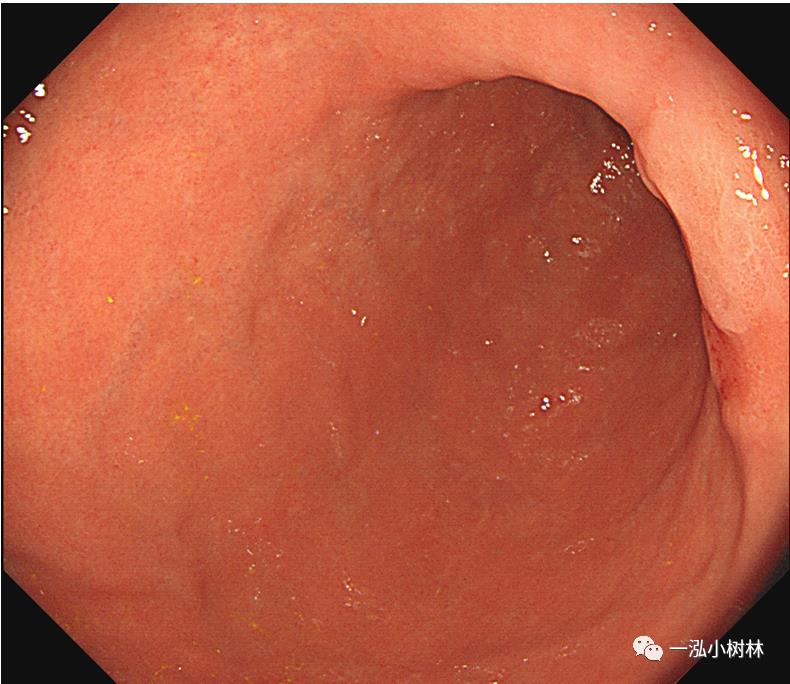

例4 胃体下部病变

图4a 白光内镜:胃体下部高分化腺癌(Tub1)